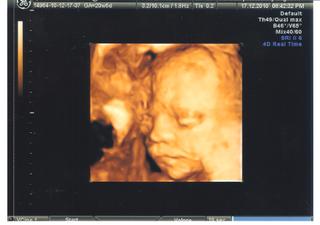

Baby, ja idem zajtra na 3D, drzte palce, aby bolo malinke v poriadku a aby sa ukazalo.. Neviem, ci vobec zaspim 😅

@buburka - gratulka k dobrym vysledkom a malicky je krasnucky, ako si spinkal 🙂